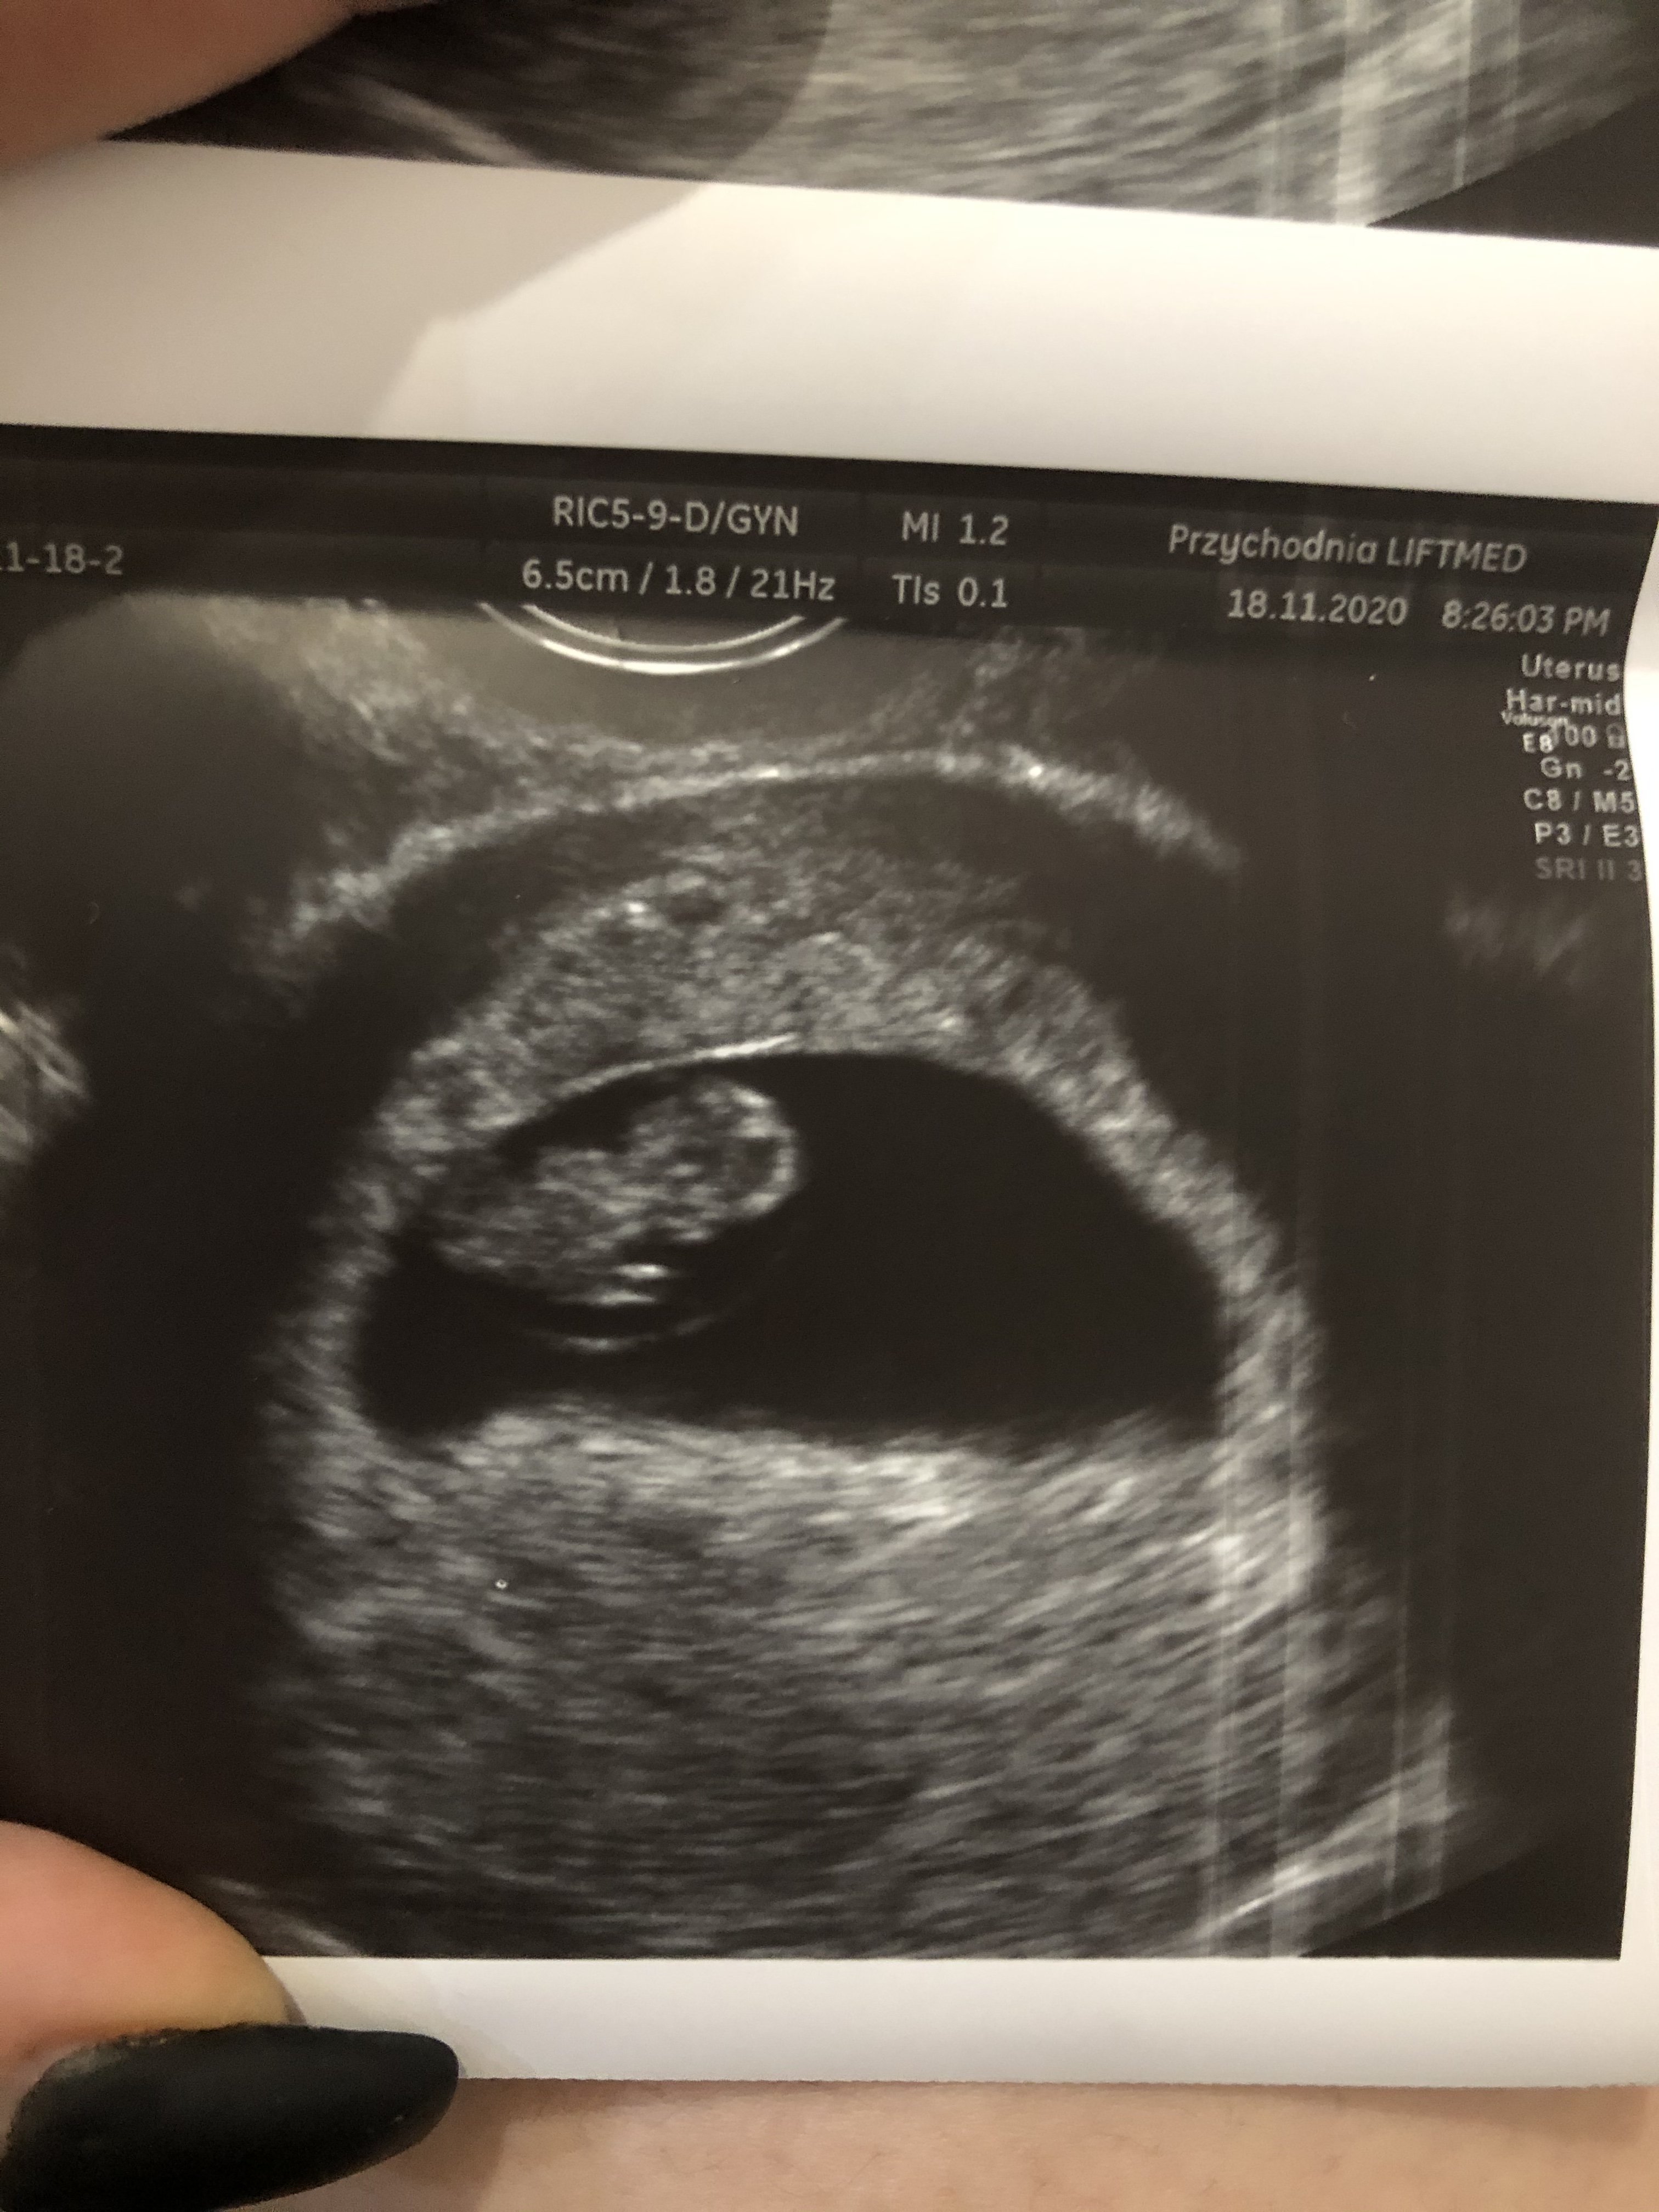

Nasze fasolki / USG